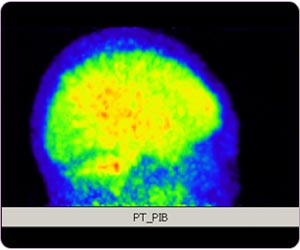

C-11 PIB PET MIP: Alzheimer disease